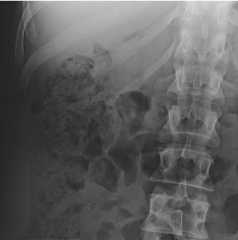

Plain abdominal radiography of patient 2

Plain abdominal X-ray of a patient showing distension of the large bowel and gas-fluid levels as signs of a large bowel obstruction (LBO)

Image: “Plain abdominal radiography of patient 2” by Department of General, Visceral, Vascular and Transplant-Surgery, Julius-Maximilians-University of Würzburg Würzburg Germany. License:CC BY 3.0